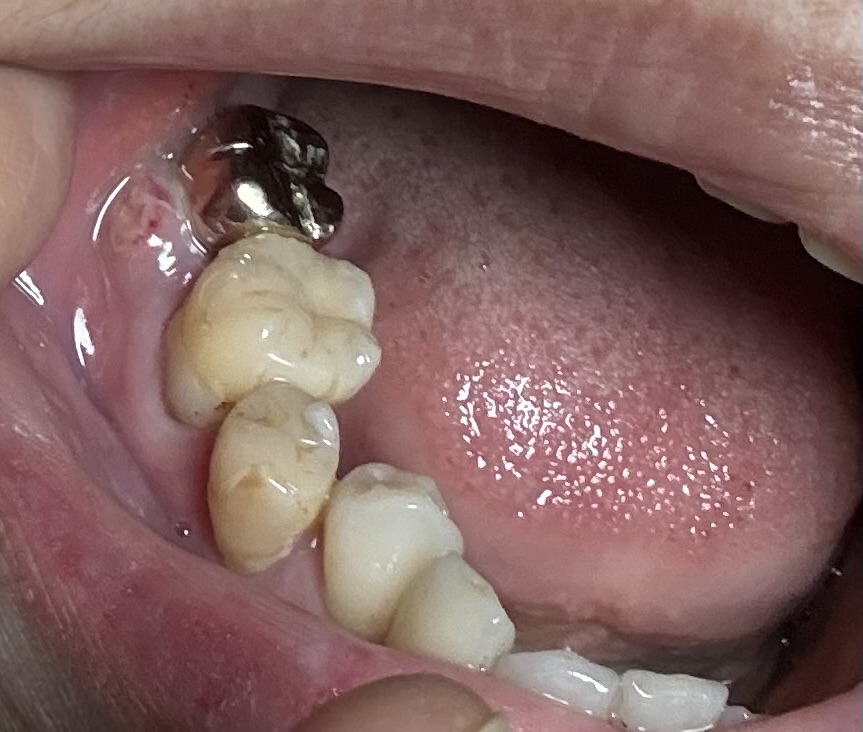

写真は歯科で切開したあと、家で撮りました。

クラウンの横のところが腫れています。

画像1

歯が弱っているというより、添付された写真から察するに、歯を支えている ( た ) 骨が弱っているものと推測します。